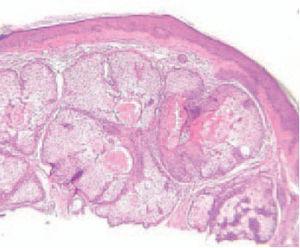

Fig. 2.—Imagen histológica. (Hematoxilinaeosina, ×10.)

El estudio histológico de una de las lesiones puso de manifiesto una epidermis adelgazada, ortoqueratósica y abundantes glándulas sebáceas normales en la dermis. Algunas de estas glándulas formaban parte de unidades pilosebáceas completas y otras no tenían folículos pilosos. Los conductos excretores estaban dilatados y ocupados en su mayoría por secreción sebácea. No se observaron signos de infección viral ni de malignidad, y se confirmó el diagnóstico clínico de hiperplasia de glándulas sebáceas.